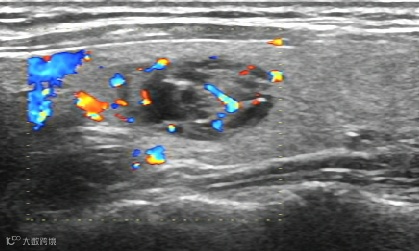

腱鞘囊肿抽液治疗:

治疗前,囊肿大小11X10mm。

治疗后,囊肿消失。